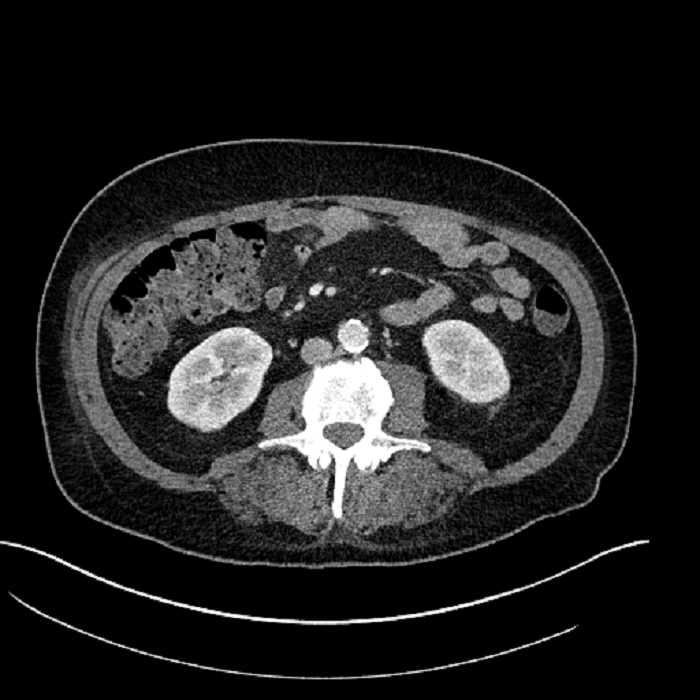

• Large fluid density structure in hepatic segments 7 and 8 measuring 10 x 7 x 7 cm with internal septation and circumferential ill-defined low density compatible with edema

• Clearly marginated fluid density structure in segment 7 and several other scattered tiny hypodensities, which likely represent cysts

Acute sigmoid diverticulitis complicated by a small contained perforation and a large abscess in the right hepatic lobe. Additional small subcapsular abscesses along the anterior margin of the left hepatic lobe.

• The classic CT imaging appearance is a double target sign with internal low density surrounded by an internal enhancing rim (capsule) and a low density external rim (edema)

Hepatic abscess showing the double target sign with low density internally surrounded by a thin inner enhancing rim (red arrow) and ill-defined outer low density rim (yellow arrow). Blue arrow indicates an internal septation. Red arrows: additional smaller subcapsular abscesses. Red arrow: focal contained perforation associated with diverticulitis.